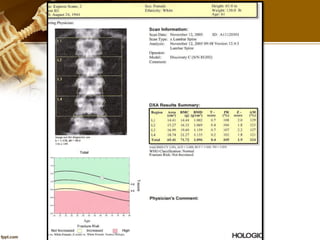

AP Lumbar Spine Exam

 Correct Spine ROI

• The spine is in the center of

the image including all L1-L4

vertebrae.

• (1) All of L4 (1) is shown.

• (2) The top of L5 (2) is shown.

• (3) Approximately lower half

of T12 (with ribs) is shown.

 Spine ROI

• Use High definition for patients

with heavy weight.

• Cover from L1-L4

• The Lines have to be parallel to

intervertebral space.

• Avoid Metals

• Delete osteophyte